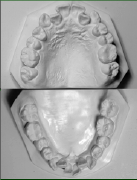

- 模型とその分析

_